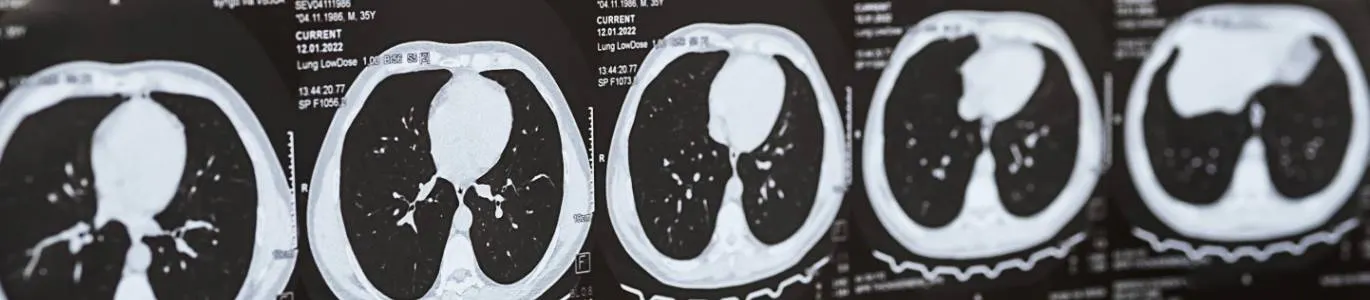

TAC de tórax